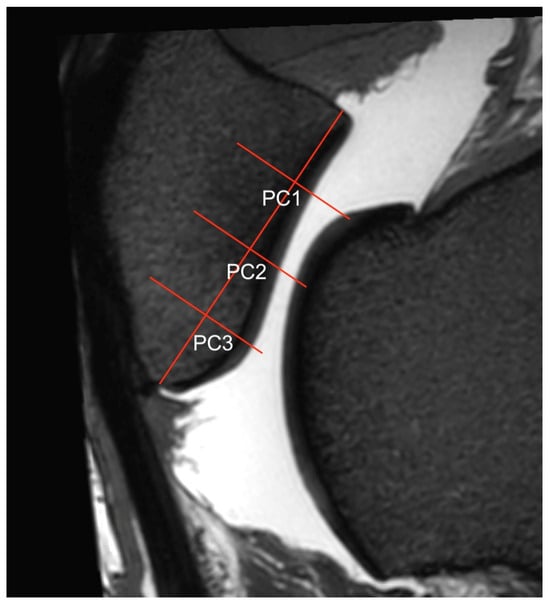

Figure 4. Sagittal view of the central ridge of the patella in a 3D T2w VIEW sequence where the regions of interest (ROIs) PC1, PC2, PC3) were measured. To determine the ROIs of the patellar cartilage, the same sagittal orientations were used as for the trochlea (Figure 1). In the transverse view, the dorsal plane was adjusted to be parallel to the patellar joint surface at the specific ROIs. This was readjusted for the ridge and each groove of the patella to account for the different orientations of the joint surfaces. In each sagittal view (grooves and ridge), the articular surface of the patella was divided into quarters, resulting in three ROIs per slice.